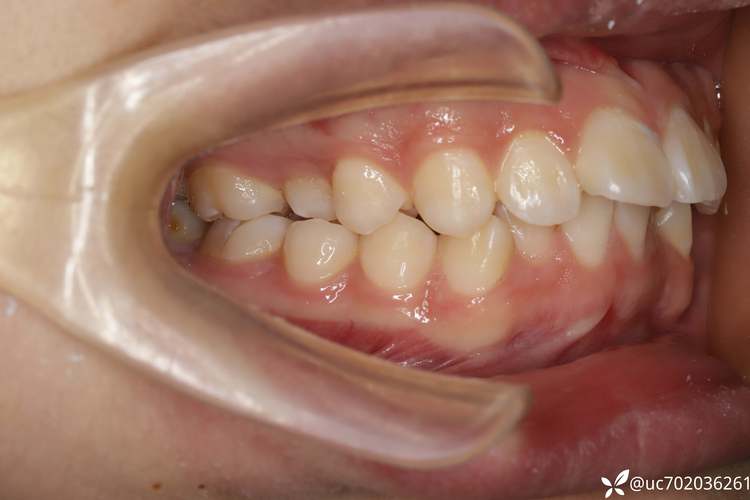

- 这是专业决策: 拔除磨牙是正畸医生基于对你口腔全面检查(包括模型、X光片、口内照片、面型分析等)后做出的专业治疗计划的一部分,医生认为拔除这颗磨牙是解决你牙齿问题的最佳或必要方案。

- 为什么选择拔这颗牙? (具体解决什么问题?拥挤程度?前突程度?咬合问题?)

- 拔牙后如何移动牙齿? (前牙内收多少?后牙前移多少?)

- 预期的治疗效果? (牙齿排列、咬合、面型改善程度)